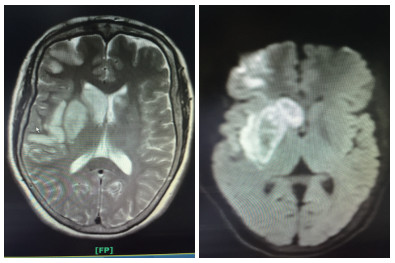

溶栓后第2天头颅MR检查

患者女性,55岁,住院号:526777。主诉:左侧肢体乏力1 h余。现病史:缘于入院前1 h余始无明显诱因出现左侧肢体乏力,持物、行走不能,伴有构音含糊,无吞咽困难、饮水呛咳,无意识障碍,无抽搐、二便失禁,无头晕头痛呕吐,无畏冷发热,无咳嗽咳痰,无心悸气喘,无腹痛腹泻,无双下肢水肿。在外未诊治,急诊行头颅CT后送入本科。既往史:无。个人史:无烟酒嗜好。体格检查, 查体:体温: 36.5℃, 脉搏: 72次/min, 呼吸: 20次/min, 血压: 126/76 mmHg。双肺呼吸音清,未闻及干湿性啰音;心率72次/min,律齐,各瓣膜区未闻及杂音;周围血管征阴性;专科查体:神志清楚,构音含糊,对答切题,双眼向右侧凝视,左侧鼻唇沟浅,口角歪向右侧,伸舌偏左,左侧肢体肌力1级,右侧肢体肌力5级,肌张力正常,深、浅感觉正常,膝反射、跟腱反射等腱反射对称活跃,克匿格征、布鲁金斯基征阴性,左侧巴彬斯基征阳性,右侧病理征未引出,共济运动及闭目难立征欠合作。NIHSS评分14分。辅助检查:头颅CT示双侧基底节区腔隙性脑梗死;入院诊断:①脑梗死②糖尿病?治疗;患者处于溶栓时间窗,入院后完善相关检查无明显溶栓禁忌证,经家属同意,予阿替普酶溶栓(患者体质量55 kg,予阿替普酶50 mg溶栓,其中5 mg静推,余剂量予1 h泵入),并予“吡拉西坦8 g静滴,1次/d,依达拉奉30 mg静滴,2次/d”等治疗,第2天患者左侧肢体乏力、构音含糊较前改善,查体:构音稍含糊,双眼无凝视,左上肢肌力1+级,左下肢肌力3级,溶栓后第1天复查颅脑CT平扫:右侧基底节区及额颞叶大面积脑梗死,并右侧基底节区出血性脑梗死可能性大(阅片考虑可疑高密度灶非出血灶,考虑正常脑组织),予加用波立维75 mg,1次/d、立普妥20 mg每晚睡前1次、尤瑞克林0.15 PNA静滴,1次/d。溶栓后第2天颅脑MR平扫(1.5T):①双侧基底节区、双额叶多发梗死灶、腔隙灶。②脑干腔隙灶?③部分空泡蝶鞍。患者住院共11 d,出院时患者左侧肢体乏力、构音含糊较前改善,查体:构音稍含糊,双眼球活动正常,左侧鼻唇沟略浅,口角略歪向右侧,伸舌略偏左,左上肢肌力2+级,左下肢肌力4+级,NIHSS评分5分。